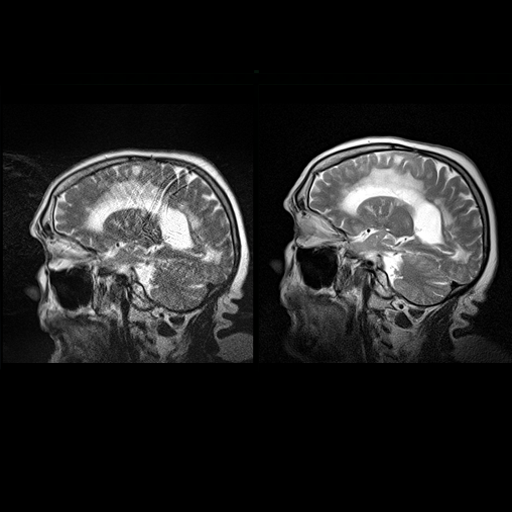

3D VRT syngo |

|

This application provides a dedicated evaluation

software for colored, volume rendered (VRT)

visualization of MR and CT data as a complement to

traditional MIP display.

The combination of automated segmentation and

easy-to-use editing tools, provides users with a rapid

way to visualize MRA and VIBE studies in their 3D

context in a clear and precise manner.

3D VRT includes tools for:

Direct Volume Rendering Technique (VRT) for viewing 3D

volumes

- Projection of volume information onto an arbitrarily

orientation plane.

- For each projection ray the density, opacity, and

refraction of the penetrated volume is evaluated and the

resulting intensity/color is recorded.

- Independent control of color, opacity and shading of

up to 4 tissue classes.

- Selection of predefined color VRT settings via an

image gallery

- User selectable visualization filters for MPR, MIP,

SSD or VRT

- Storage and filming of reconstructed images or ranges

Editing Functions to create and modify segmented objects

- Segmentation of 3D datasets either with manual contour

creation, by thresholding, or by volume growing

operations.

- Volume measurements